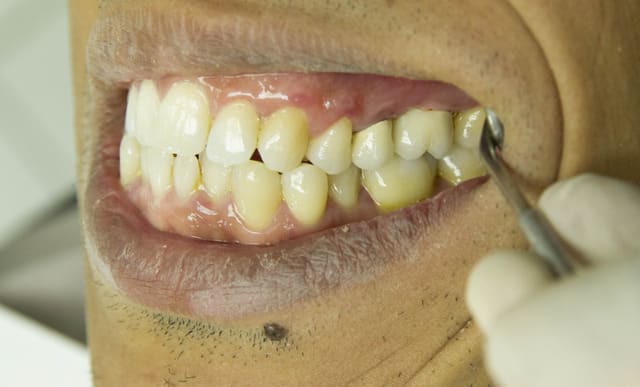

Dans un cas comme celui ci , il est certain qu'en partant du principe que le certissage périphérique est la seule solution, il ne reste plus qu'à dépulper la dent et mettre un IC, avec 0 parois résiduelles, bref, le top pour une 25.

En prenant le problème à l'envers , en gardant ce qui est conservable (la pulpe et les 2 mm des parois cervicales vestibulaires et linguales) , il est possible aujourd'hui , avec les techniques de collage , de restaurer des dents, sans avoir à réaliser d'endos à visée prothétique.

Dans une dizaine d'année, il sera toujours possible de refaire un onlay et peut être un IC et une CCM dans 20 ans et un implant dans 30...

Par contre cette prémo à 0 parois résiduelles reconstituée par IC + CCM , je ne me risquerai pas à pronostiquer 20 ans....

Nos traitements ne sont pas éternels , mais en étant plus conservateur , et en suivant le gradient thérapeutique , nous pouvons repousser les limites plus loin, et faire gagner des années aux dents den nos patients.

Enfin dans ce cas bien précis nous sommes tout d'accord pour dire que l'endo est parfaite ! La pulpe étant la meilleure obturation canalaire.